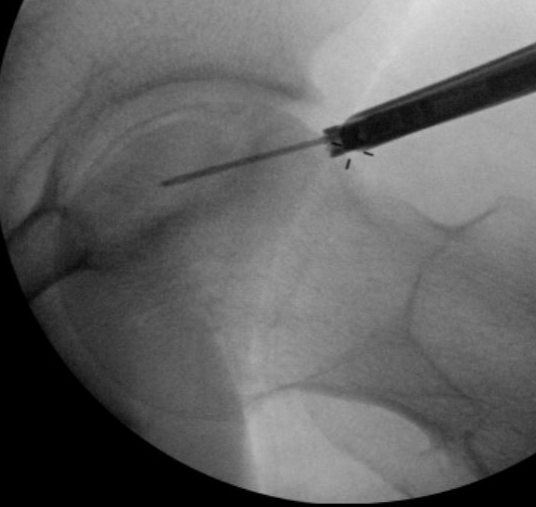

Technique

- AP and lateral xray

- entry point through greater trochanter

- above lesser trochanter to reduce fracture risk

- enter site of AVN

- overdrill

- +/- bone graft / vascularized bone graft / tantalum rod / BMAC (bone marrow aspirate concentrate)